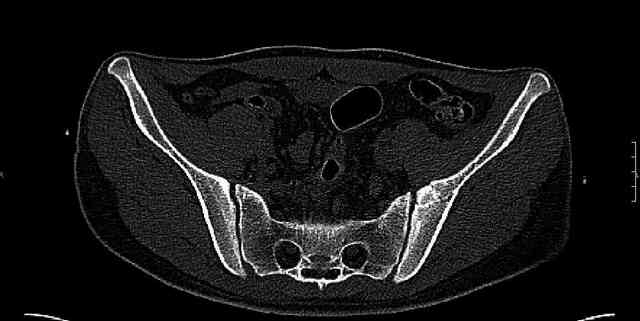

Re: Нелеченный перелом вертлужной впадины

Some more images. Does it help to guess which part of the acetabulum is displaced?